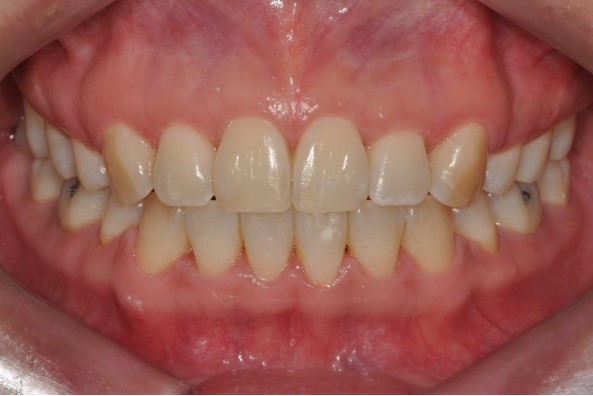

실제 환자 케이스로 보는 치간삭제 활용

정리해 보면 치간삭제는 다음과 같은 상황에서 특히 유용합니다.

비발치 교정에서 부족한 공간을 확보하고 싶을 때

위·아래 치아 크기 비율을 맞춰 교합을 안정적으로 형성하고 싶을 때

치간공극(블랙 트라이앵글)을 줄이고 심미성을 높이고 싶을 때

울퉁불퉁한 접촉면을 매끈하게 정리해 안정성을 높이고 싶을 때

위에서 소개해 드린 사례들처럼, 교정치료 과정에서 치간삭제를 적절히 사용하면

발치 없이도 치열을 정리할 수 있고,